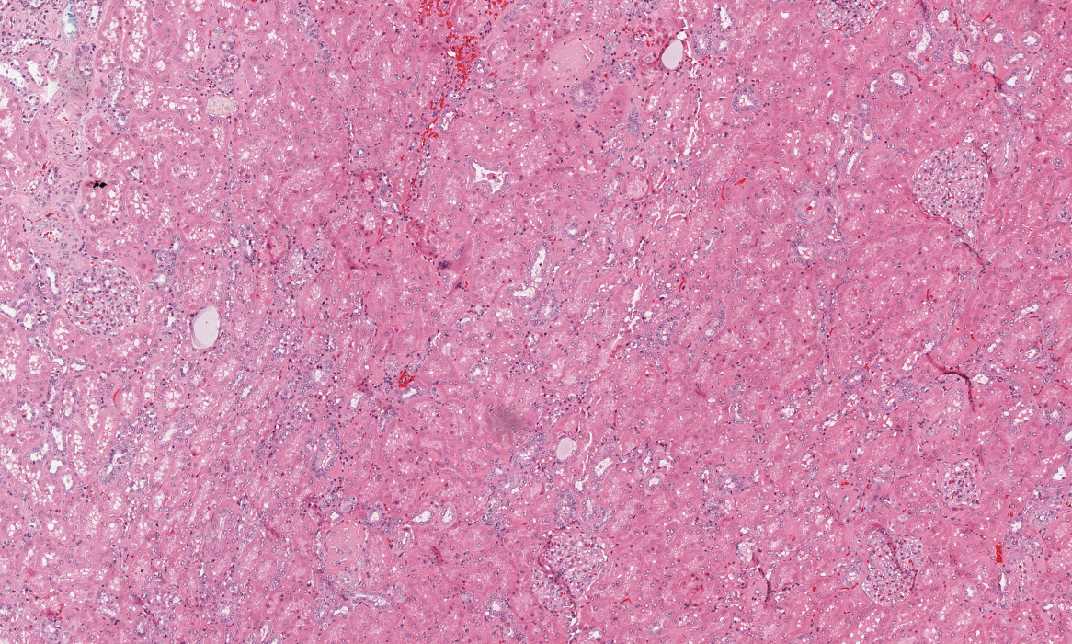

Hematoxylin & eosin

Area 1: This image is taken from the residual renal parenchyma and many glomeruli are present.

• This is a kidney and residual renal parenchyma is present at the periphery of the tumor (Area 1).